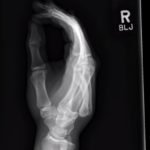

A two-view radiograph of the right hand was obtained which revealed a dorsal dislocation of the distal fourth and fifth metacarpals (see red and blue outline, respectively) with a concomitant fracture of the distal fifth metacarpal (see yellow line) and avulsion fracture of the lateral aspect of the hamate (see green line). After reduction the fourth and fifth metacarpal dislocations are resolved; however, the distal fifth metacarpal fracture (yellow line) and avulsion fracture of the lateral aspect of the hamate (green line) are still visible.

In a case series including 21 patients, dorsal dislocation of carpometacarpal joints was initially missed in 15 of these cases.1 This is often due to the overall swelling that may mask the ulnar deformity as well as failure to obtain a true lateral X-ray.This is a rare injury because there are many strong supporting ligaments.2 The dislocation requires closed reduction, with application of ventral longitudinal pressure and traction of fourth and fifth digit.3 There is debate amongst hand surgeons if closed reduction followed by casting or open reduction is superior, but there have been no large-scale studies comparing treatment options.4 Post-reduction films were obtained and an ulnar gutter splint was placed. The patient was instructed to follow up with hand surgery in the next week.